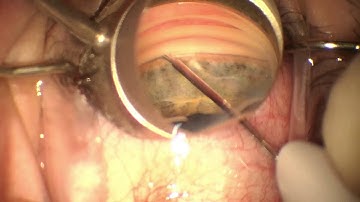

Glaukos iStent placement after Restor IOL by Steven G. Safran